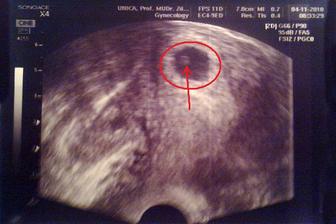

Tak to vše začalo.....